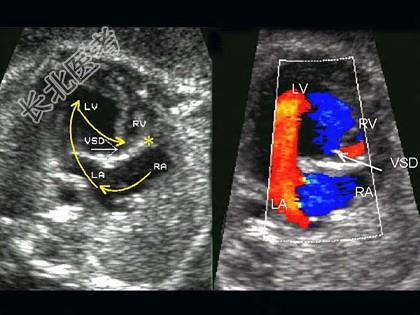

- 单项选择题女孩,9岁。平时乏力, 活动后气促,胸骨左缘第3~4肋间闻及Ⅲ~Ⅳ级全收缩期杂音, 经超声心动图检查,如图, 确诊为先心病,室间隔缺损。下列哪项不是其常见并发症  (    )